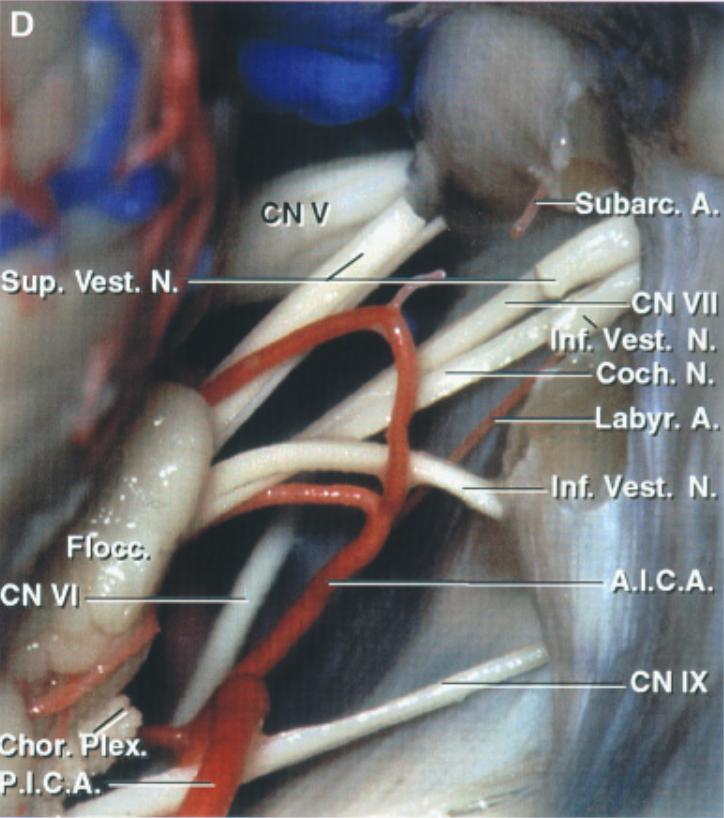

Nervus trigeminus retrosigmoidal

Darstellung des Nervus trigeminus und der Anatomie des Kleinhirnbrückenwinkels in der Ansicht eines retrosigmoidalen Zugangs. Abbildung adaptiert von Rhoton Jr Albert L. The cerebellopontine angle and posterior fossa cranial nerves by the retrosigmoid approach. Neurosurgery 47.3 (2000) S93-S129.